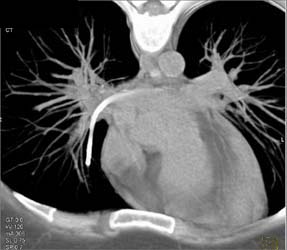

Mai Infection in 3D